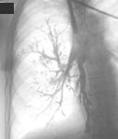

При екзобронхіальному

рості пухлини (рис.5) на початку захворювання немає ні клінічних ні

рентгенологічних проявів. Поки діаметр вузла не стане більше діаметру великих

гілок легеневої артерії чи вени, він не диференцюється. По мірі розвитку

пухлини і інфільтрації стінки бронху також виникають гіповентиляція, клапанна

емфізема і ателектаз. Їх рентгенологічні ознаки такі ж самі, як і при

ендобронхіальному рості пухлини, але в даному випадку ще візуалізується тінь

екзобронхіального раку. При КТ дослідженні на зрізі кореня легені вже на

початкових стадіях можна виявити відображення вузла, розташованого асиметрично

і пов¢язаного зі стінкою бронху. При збільшенні пухлини до декількох

сантиметрів і швидкому метастазуванні в лімфовузли корень виглядає

поліциклічним, що іноді враховується як системне ураження лімфовузлів легені та

середостіння. При подальшому рості раковий вузол починає розповсюджуватися по

ходу бронхів та судин, що проявляється на рентгенограммах грубими тяжами - „променями”.